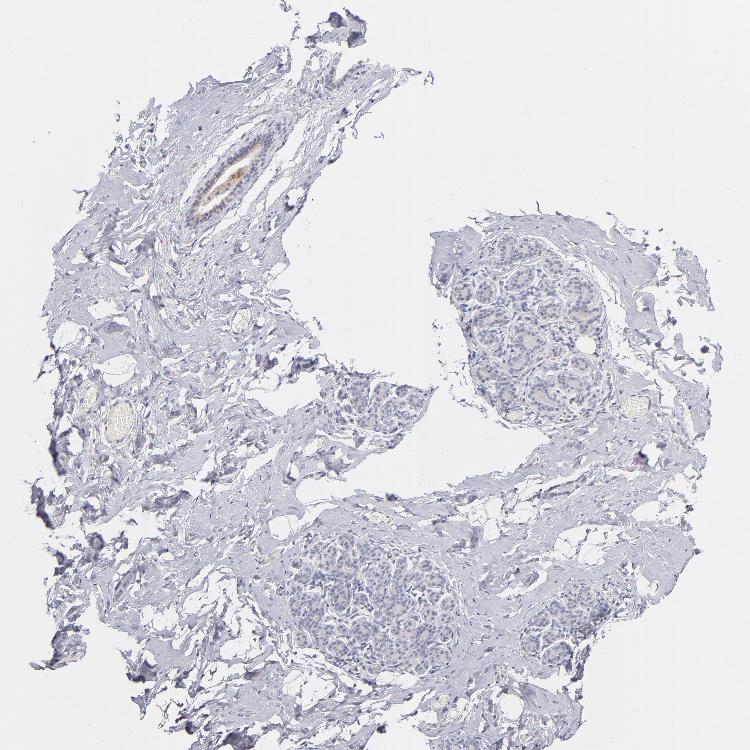

BREAST - Antibody stainingi

Antibody staining in the annotated cell types in the current human tissue is reported as not detected, low, medium, or high, based on conventional immunohistochemistry profiling in selected tissues. This score is based on the combination of the staining intensity and fraction of stained cells.

Each image is clickable and will lead to virtual microscopy that enables deeper exploration of all samples and also displays staining intensity scores, fraction scores and subcellular localization as well as patient and tissue information for each sample.

Antibody HPA045168Antibody CAB000147Antibody CAB003839Antibody CAB003840Antibody CAB075726Antibody CAB075727

Adipocytes MediumNot detectedNot detectedMediumHighHigh

Glandular cells HighNot detectedNot detected-MediumMedium

Myoepithelial cells HighNot detectedNot detected-MediumMedium